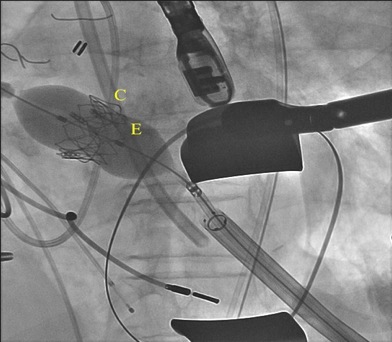

Shortly after transfer, the patient underwent valve-in-valve TAVR within the previous bioprosthetic aortic valve while under general anesthesia (Figures 3 and 4). The procedure was performed via a transapical approach, as she was not a candidate for a transfemoral approach due to the small size of her femoral arteries. To enable left ventricular transapical access, an approximately 2- to 3-inch left thoracotomy was performed. An 18-gauge needle was introduced in the distal anterolateral wall of the left ventricle near the apex, and a 0.035-inch J-tipped guidewire was introduced in the left ventricle. The needle was removed and a 7 French (Fr) sheath was introduced in the left ventricle over the guidewire. The guidewire was then advanced across the aortic valve into the ascending aorta. A 6-Fr Judkins right number 4 (JR4) catheter was introduced over the guidewire, the guidewire and JR4 catheter were advanced into the descending aorta, and the guidewire was exchanged for a 0.035-inch Amplatz extra-stiff guidewire. The JR4 catheter and 7 Fr sheath were removed and the Edwards 24 Fr Ascendra sheath was introduced in the left ventricle. A 23-mm Edwards Sapien XT valve was introduced over the guidewire across the bioprosthetic aortic valve and was successfully deployed under rapid ventricular pacing at 180 beats per minute. The delivery catheter was then removed. Simultaneous left ventricular and aortic pressures revealed a mean aortic valve gradient of only 5 mm Hg. The valve function was evaluated by transesophageal echocardiography and found to be normal without paravalvular regurgitation. The Ascendra sheath was removed, and the left ventriculotomy and left thoracotomy were successfully closed. The patient was transferred to the cardiovascular intensive care unit and was extubated soon after the procedure. She had an uneventful recovery. Within 2 days following the procedure, the patient was able to ambulate independently. Her antihypertensive and diuretic medication doses were reduced from her prehospitalization doses and she was subsequently discharged to home.

Figure 3. Fluoroscopy demonstrating a 23-mm Edwards Sapien XT valve (E) positioned across a 21-mm Carpentier-Edwards perimount aortic pericardial bioprosthesis (C) via a transapical approach.

Figure 4. Valve-in-valve deployment of a 23-mm Edwards Sapien XT transcatheter valve (E) to replace the degenerated 21-mm Carpentier-Edwards perimount aortic pericardial bioprosthesis (C) via a transapical approach.